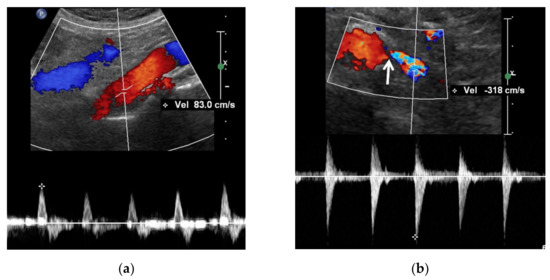

5.2. Color Doppler US

Color Doppler US shows mainly blue or red signals in the normal renal artery. The brightness of these signals is increased in the renal artery (Table 4). The speed of blood flow increases as RAS becomes severe (Figure 3). These Doppler signals show mixed bright red and bright blue colors in the poststenotic dilatation because turbulence is created from the back-and-forth high-speed blood flows out of the stenosis by means of colliding with the lumen of renal artery (Figure 2 and Figure 3).

Color Doppler US of the kidneys is not an ideal approach for detecting RAS. Renal perfusion can be normal in early stage RAS (Figure 4) and decreases in intermediate or late-stage RAS. Renal perfusion is an indirect finding suggesting RAS. Accordingly, it is not adequately sensitive for detecting early stage RAS.

Spectral Doppler US quantitatively measures the velocity of blood flow in the stenotic renal artery (Table 4). The peak systolic velocity (PSV) within the stenotic renal artery is frequently more than 180–200 cm/s [4,22,23,24,25,48] (Figure 2 and Figure 3). If PSV is more than 180 cm/s, the sensitivity and specificity for RAS range from 85–97% and 72–98%, respectively [24,25,28,31]. In case of unilateral RAS, PSV is significantly different between the two renal arteries. At this point, two simple concepts should be kept in mind: first, the normal PSV values in normal renal arteries without stenosis (about 70–100 cm/s), and, second, angle correction is essential to obtain reproducible and accurate measurements of PSVs. If the PSV of the renal artery is ≥3.5-fold that of the aorta (renal-to-aorta ratio (RAR)), it can suggest RAS [26,27,29,49] (Figure 4). The PSV RAR is another good indicator for identifying RAS. If RAR is 3.5 or greater, the sensitivity and specificity ranges are 91–92% and 71–95%, respectively [26,27,29]. It is important to determine where PSV is measured within the aorta because it differs by region-of-interest location. First, radiologists or sonographers should find the origin of the superior mesenteric artery (SMA) during the sagittal US scan; then, the PSV region of interest should be 1–2 cm below the SMA because the renal arteries are located below the origin of the SMA.

The frequency shift from the stenotic artery is not easy to detect with spectral Doppler US as it tends to be small (Figure 2 and Figure 3). There are some technical tips in assessing RAS: First, the critical angle between the renal artery flow and US from transducer should be observed when a good spectrum of arterial flow is not obtained. The optimal critical angle should be kept at 30–60° for detecting a good frequency shift [48]. Second, the sample volume size should be higher than that of the RAS to oversample frequency shifts. The renal artery spectrum can be identified by means of evaluating the flow direction and spectral pattern from among the various spectra given by arteries and veins. Third, the PSV of the renal artery should be measured in the poststenotic dilatation when a good spectrum cannot be obtained in the stenosis (Figure 2 and Figure 3). If the PSV is more than 180–200 cm/s, it will be higher in the stenotic artery. If RAS is severe, the frequency shifts are too weak to directly detect from the stenotic artery [23,49].